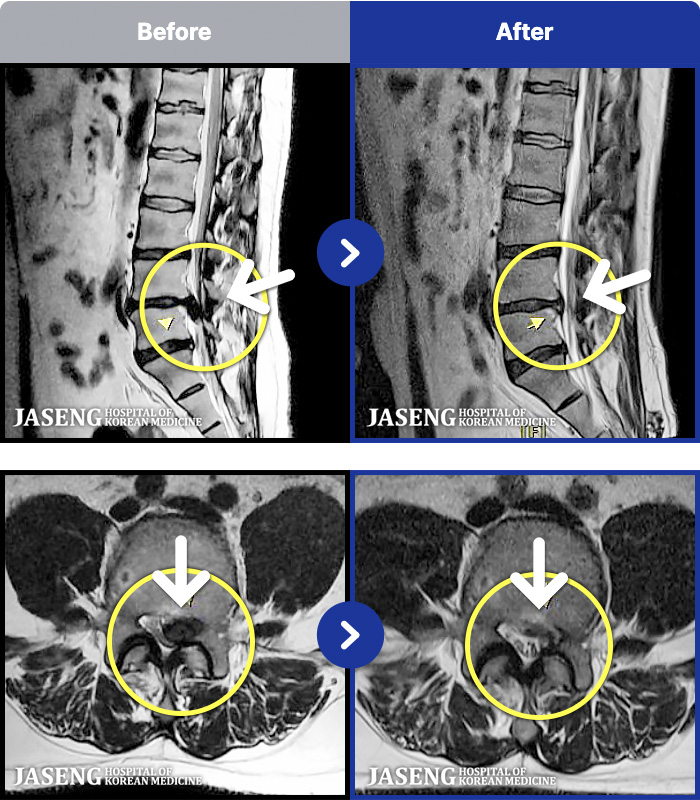

97 MRI ũ ʸ Ȯϼ.

ȯںп Ǹ ǿ ԿǾ, ο ġ ۿ Ƿ ġḦ Ͻñ ٶϴ.